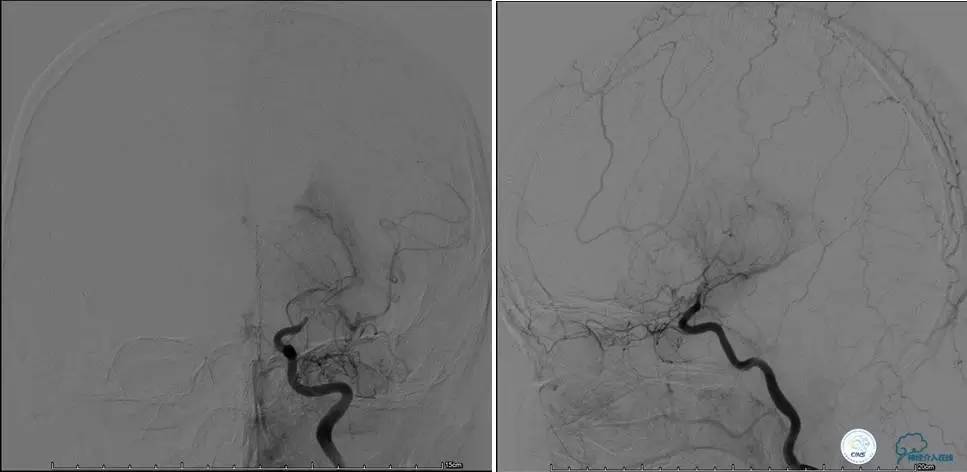

▼DSA示右侧椎动脉发育低下,弥漫性狭窄,可以看到左侧椎动脉反流,因此判断左侧椎动脉V4段CTO。

微导丝穿过闭塞段,微导管造影,球扩闭塞段,置入Wingspan支架,血流完全恢复正常。

患者术后2天再次出现卒中发作,药物治疗好转,此后病情稳定。半年后复查DSA,见支架闭塞,侧支循环开放。患者一般情况好,mRS:1分。